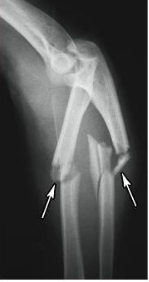

displaced and non displaced fracture